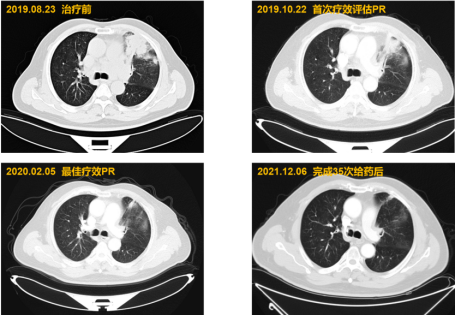

2019.09.12起阿得贝利单抗+EC治疗6周期

2019.10.22门诊胸部CT检查,疗效评估为PR

2020.02.06起阿得贝利单抗单药维持29周期

2021.12.06完成35次给药出组,随访

截至2023.3 患者仍存活,总生存期超过42个月